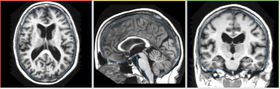

Segmentation Results

This module computes voxel by voxel tissue classification of an MR brain image using a fuzzy c-means algortihm. Bias field is modeled as a lower order polynomial. Bias field and tissue classification are estimated iteratively in an EM fashion. Internally, each voxel is assigned tissue membership function values, which range from 0 to 1. At any voxel, the sum of membership function of all classes is either 0 (outside of brain), or 1. The membership functions are converted in tissue labels to generate hard segmentation.

This module is typically used to assign tissue labels to an image. For example, in MR brain image analysis, many applications need to know which voxels belong to gray matter, white matter, and CSF.